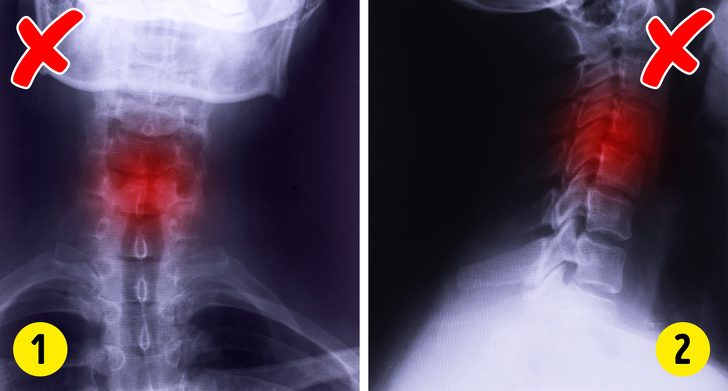

Остеохондроз

Все проблемы с позвоночником у нас обычно называют остеохондрозом. Есть даже шутка, что слово «конек-горбунок» переводится на английский как horse-osteohondros (лошадь с остеохондрозом). Ну а если серьезно, то за остеохондрозом скрываются такие заболевания, как:

Грыжи межпозвоночных дисков (тут нужно серьезное лечение вплоть до операции).

Миозит (спазм и воспаление мышцы).

Фибромиалгия (характерна боль во всем теле).

Все эти диагнозы реальны, и при каждом из них назначается абсолютно разное лечение.

Что делать:

Обязательно пройдите такие медицинские процедуры, как:

МРТ;

УЗИ суставов.